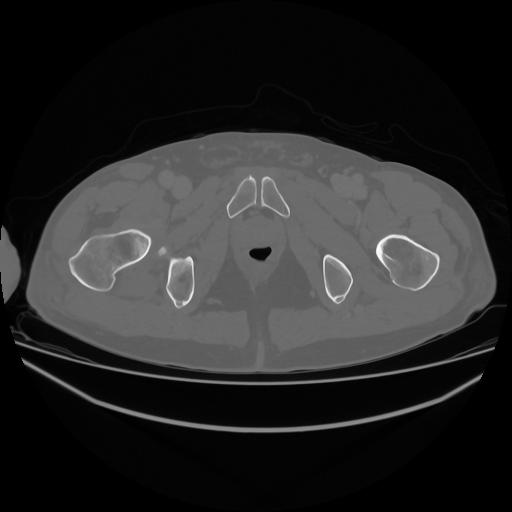

5 CUERPO,CE,Vol,1.0,CUERPO,,